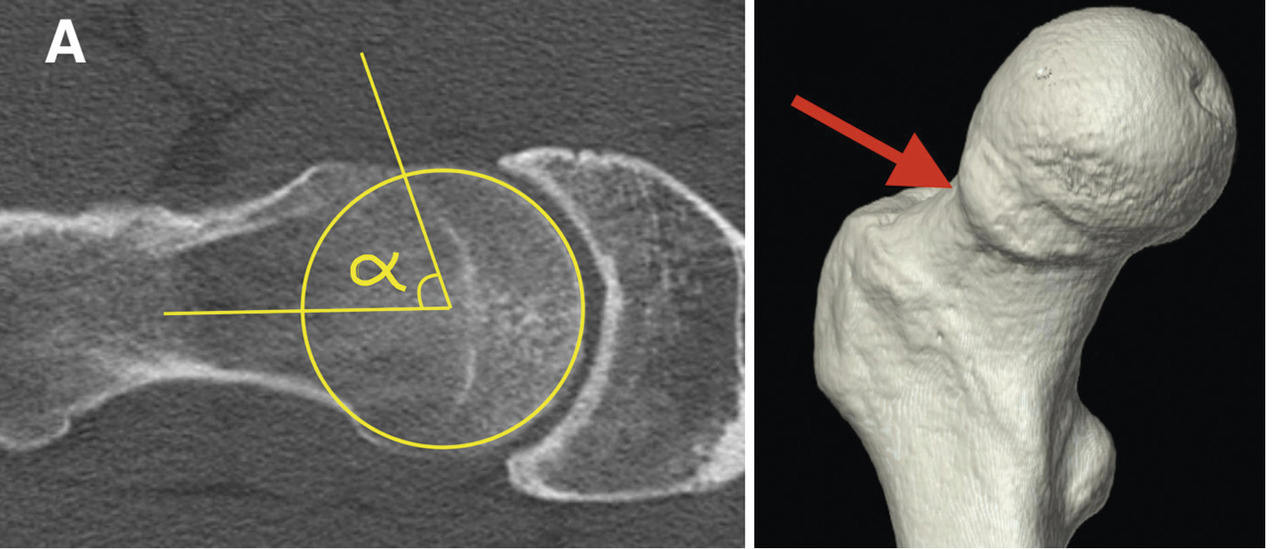

L’association de symptômes douloureux et de radiographies évocatrices confirme le diagnostic. Une imagerie en coupes et injectée (arthroscanner ou arthro-IRM) précise les lésions cartilagineuses et labrales. Une reconstruction 3D montre la bosse fémorale en vue d’une éventuelle résection (fig. 1).